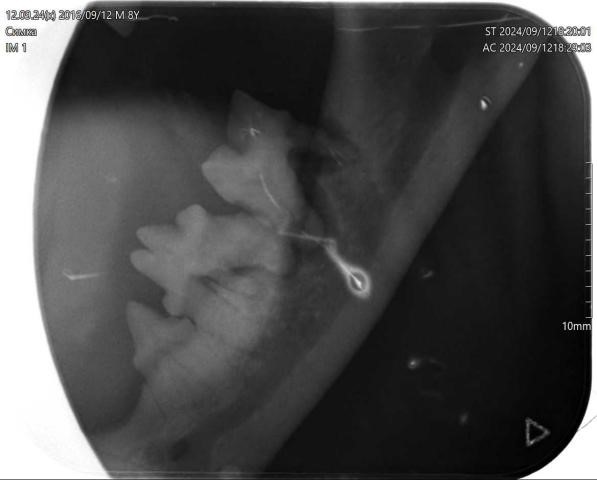

Геминация зубов у восьмилетней кошки бурманской породы